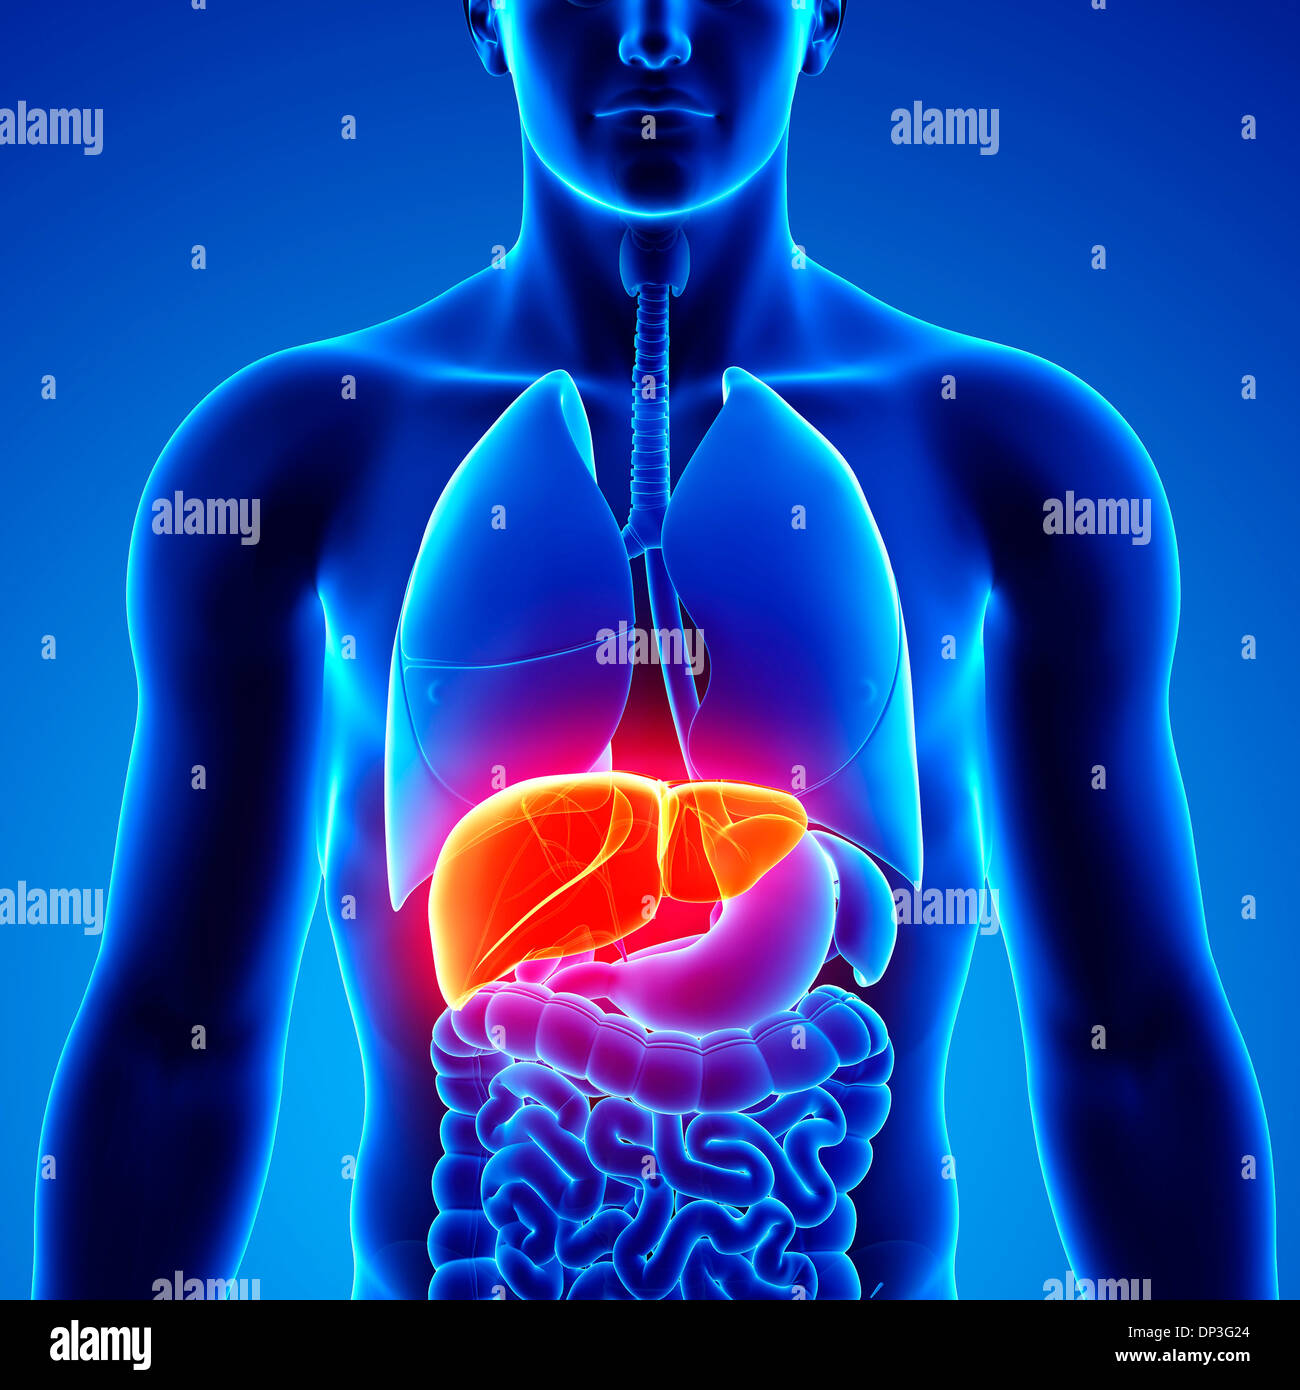

RF2GB8D4J–3D-Darstellung des Verdauungssystems der männlichen Anatomie, zusammen mit anderen inneren Organen. Glasbild auf blauem Hintergrund, Vorderansicht.